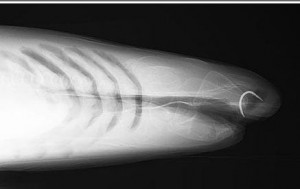

Florence est le premier requin à avoir rencontré la célébrité car le premier à avoir bénéficé d’une opération de chirurgie en Angleterre. Il s’agissait d’enlever un hameçon rouillé coincé dans le haut de sa mâchoire.

Le coté délicat de l’opération a résidé, non dans son caractère technique, plutôt simple, mais dans le dosage de précision de l’anesthésie générale. Trop ou trop peu d’anesthésiant aurait pu nuire au requin ou bien le faire refermer la mâchoire sur les mains du chirurgien.

Le requin Florence en pleine chirurgie